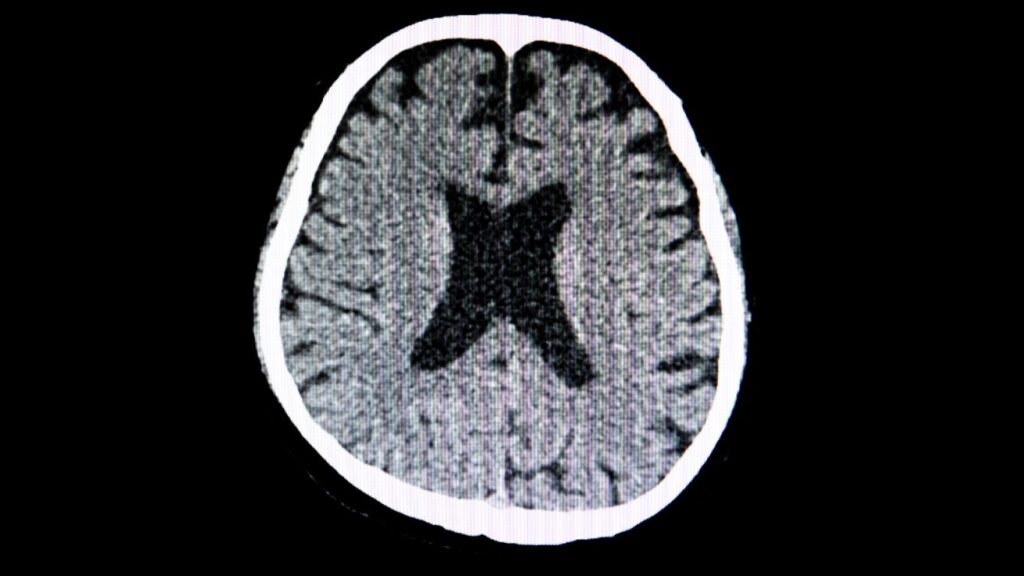

Tomografía de Cráneo – Diagnóstico Preciso en Puebla

La tomografía de cráneo se ha consolidado como una herramienta fundamental en el ámbito del diagnóstico médico, especialmente para la detección de diversas afecciones cerebrales. En Puebla, nosotros en el Hospital Guadalupe ofrecemos un servicio de tomografía computarizada que incorpora tecnología de vanguardia y un equipo de personal altamente capacitado. Nuestro compromiso es proporcionar un diagnóstico […]

Tomografía Computarizada Avanzada en Puebla

En el ámbito del diagnóstico por imagen, la tomografía computarizada se ha posicionado como una técnica fundamental que brinda resultados precisos y rápidos. En Puebla, el Hospital Guadalupe se destaca por ofrecer tomografía computarizada de última generación, garantizando la eficacia en la obtención de imágenes médicas. Esta herramienta se ha convertido en una aliada indispensable en nuestra […]